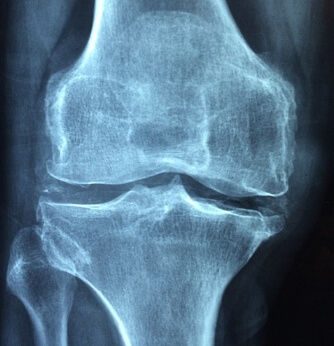

관절염의 환자 수가 연 300만 명을 넘을 정도로 일반화되고 있으며, 나이를 먹으면서 노령층에 집중되었다고 알려진 환자가 젊은 층을 중심으로도 계속 증가되고 있습니다. 이는 생활습관에 의한 영향으로 특히, 젊은 층의 액티비티 활동과 과도한 스포츠 활동 등에 영향을 받아서 관절에 염증이 생기거나 손상을 입어서 관절염으로 발전하는 경우가 많기 때문입니다. 관절염은 다양한 원인에 의해서 유발되는데, 이번 포스팅에서는 관절염을 예방하는 방법과 도움이 되는 좋은 음식을 소개해 드리면서 생활 속에서 관리할 수 있는 방법을 중심으로 알아보겠습니다.

관절염은 극심한 통증을 유발하고 일상 생활을 하는데 많은 불편함을 주기 때문에 평상시에 관절염을 예방하기 위한 개인 관리가 무엇보다 중요합니다. 아래에서 예방을 위한 효과적인 방법을 알아보도록 하겠습니다.

관절염의 예방은 관절염 관리에 매우 중요합니다. 일부 원인에 대해서는 예방이 어려울 수 있으나 대부분의 다양한 원인에 대해서는 생활습관 개선을 통해서 관절염의 위험을 최소화할 수 있습니다, 아래에서 확인해 보시기 바랍니다.